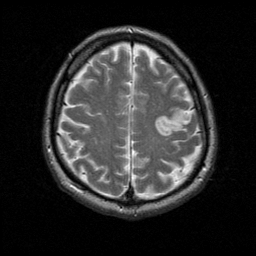

MR Study #1 -- Slice #18

Tour 1: Next/Previous/Start: The infarct also has high signal on the T2-weighted images. This slice also demonstrates the ribbon-like geometry of the lesion.

[Home][Help][Clinical][Tour 1] Slice 18